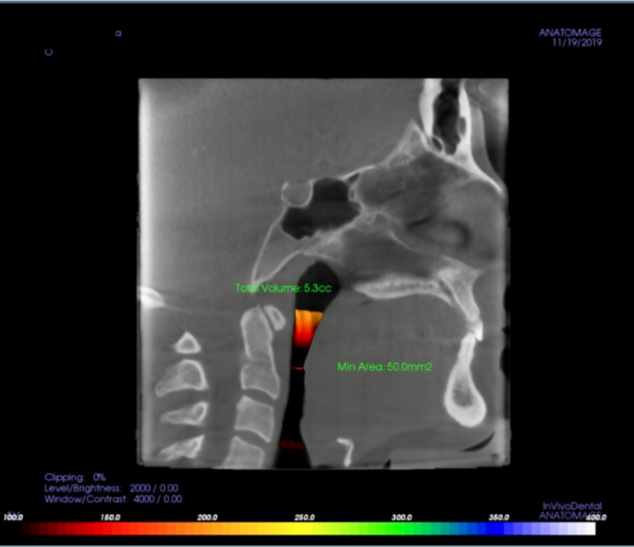

Most airway courses stop at "awareness" or devices. AMD Academy gives you a full clinical system: 3D Jaw Diagnostics®, Epigenetic Oral Appliance design, mentored cases and a path to Certified AMD status.